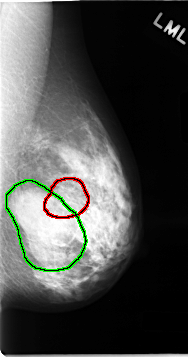

C_0062_1.LEFT_CC

FILE: C_0062_1.LEFT_CC.OVERLAY

TOTAL_ABNORMALITIES 2

ABNORMALITY 1

LESION_TYPE MASS SHAPE OVAL MARGINS CIRCUMSCRIBED

ASSESSMENT 3

SUBTLETY 5

PATHOLOGY BENIGN

TOTAL_OUTLINES 1

BOUNDARY

ABNORMALITY 2

LESION_TYPE MASS SHAPE ARCHITECTURAL_DISTORTION MARGINS SPICULATED

ASSESSMENT 5

PATHOLOGY MALIGNANT